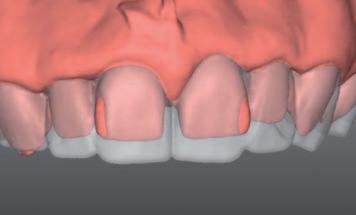

n On the basis of a facially driven smile design, with a patient-centred outcome in mind, contours of the underlying dentition that will impede the achievement of an idealised prosthodontic outcome are identified (Figure 1A) and planned for preparation with a custom digitally designed tooth reduction guide (Figure 1B). This guide is fabricated in a flexible, machinable polycarbonate material (Temp Premium Flexible, Zirkonzahn Srl, Gais, Italy) (Figure 1C).

FIGURE 1: Starting with the end goal in mind, a facially driven digital smile design reveals that the underlying tilting, drifting, rotations and maxillo-mandibular relations of the natural dentition will preclude the development of harmoniously contoured definitive restorations. A tooth preparation guide may be designed and milled at this early stage to assist in conservatively eliminating anticipated interferences, in a highly controlled workflow.

A C B